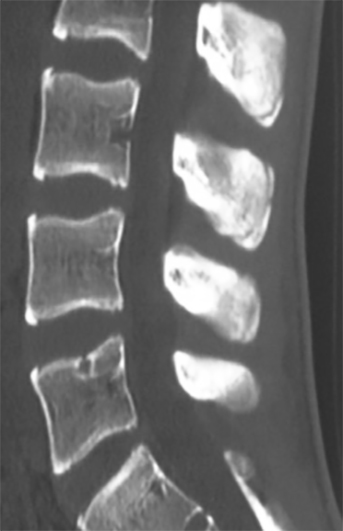

En la radiografía simple se observó esclerosis y desplazamiento del centro de osificación secundario de las apófisis espinosas L2, L3 y L4 con esclerosis del fragmento y fragmentación en L3, imágenes que recordaban a la enfermedad de Sever del calcáneo (Figura 1). Se realizó una gammagrafía con Tc99 donde se apreció hipercaptación a nivel de apófisis espinosas de L2, L3 y L4 (Figura 2) y TAC donde se confirman las lesiones (Figura 3).

Figura 3: Figura 3 Tomografía axial computarizada, corte sagital de columna Lumbar, se observan focos de apofisitis en L3-L4-L5.